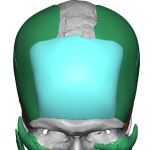

“Aesthetic temporal reduction” (often called temporal narrowing surgery) is a niche craniofacial procedure aimed at reducing the width of the head in the temple region (the area above and slightly behind the eyes). What it targets The temporal region (sides of the skull) Specifically: Temporal bone (outer skull) Temporalis muscle (a chewing muscle that can add bulk) How it’s done Read More…